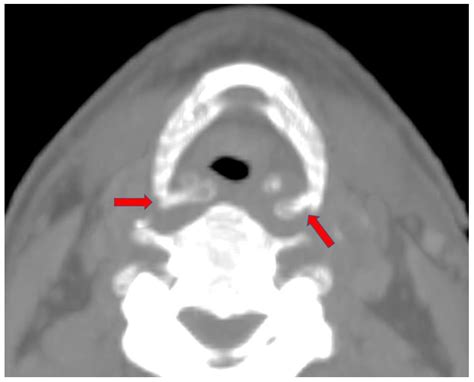

Imaging techniques play a pivotal role in the diagnosis and management of hyoid bone-related conditions. Among these, the Hyoid Bone Coronal CT scan is particularly valuable. This imaging modality provides detailed cross-sectional views of the hyoid bone and surrounding structures, aiding in the accurate diagnosis of various pathologies.

Interpretation of Hyoid Bone Coronal CT

Interpreting a Hyoid Bone Coronal CT scan requires a thorough understanding of the normal anatomy and potential pathological findings. Key points to consider include:

• Bone Structure: Assess the integrity of the hyoid bone, looking for fractures, erosions, or other abnormalities.

• Soft Tissues: Evaluate the surrounding soft tissues for masses, infections, or other pathological changes.

• Muscles and Ligaments: Examine the muscles and ligaments attached to the hyoid bone for any signs of injury or inflammation.

Radiologists often use a systematic approach to ensure that all relevant structures are carefully evaluated. This includes comparing the findings with previous imaging studies, if available, to detect any interval changes.

Fractures

Fractures of the hyoid bone are often seen in cases of blunt trauma to the neck. These fractures can be classified based on their location and pattern:

• Body Fractures: Fractures involving the central part of the hyoid bone.

• Cornual Fractures: Fractures affecting the greater or lesser cornua.

• Comminuted Fractures: Multiple fracture fragments.

Accurate identification of hyoid bone fractures is crucial for guiding appropriate management and preventing complications.